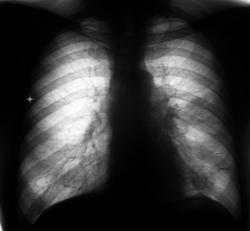

Рентгенограммы и их фрагменты.

После проведенного рентгенологического исследования органов грудной полости - рентгенографии и томографии, при которой были выявлены увеличенные лимфатические узлы в корнях лёгких и средостении, было проведено рентгенотелевидение пищевода с прицельной рентгенографией и исследованием пищевода на трохоскопе, с контрастированием пищевода водной взвесью сернокислого бария "различной консистенции" - от сверхжидкого - до пастообразного, для "выяснения состояния" заднего средостения. Была зарегистрирована и документирована "локальная деформация пищевода" на протяжении 9,5 см. с перестройкой структуры "рельфа слизистой оболочки".